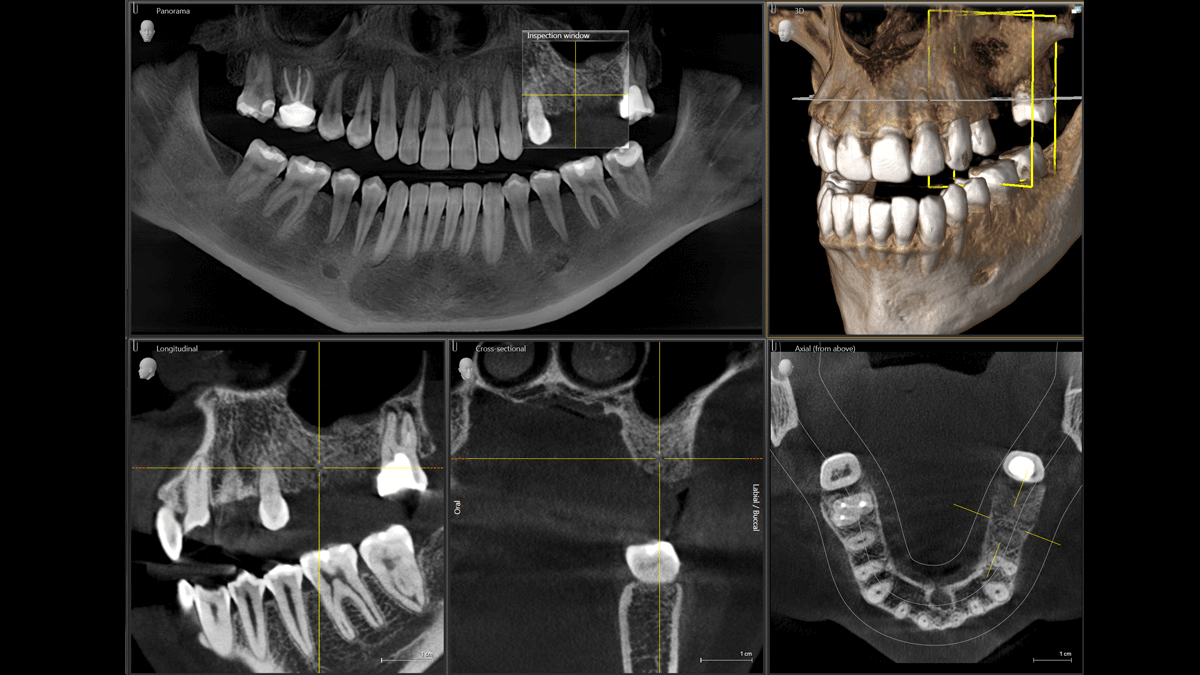

These scanners, equipped with a rotating C-arm, an X-ray image intensifier containing an x-ray source and detector, are used to achieve a more precise treatment that regular dental or facial X-rays are not able to obtain.

The main procedure involves capturing a patient’s data by scanning and generating 3-D images of dental structures, soft tissues, nerve paths, and abnormalities in the craniofacial region.